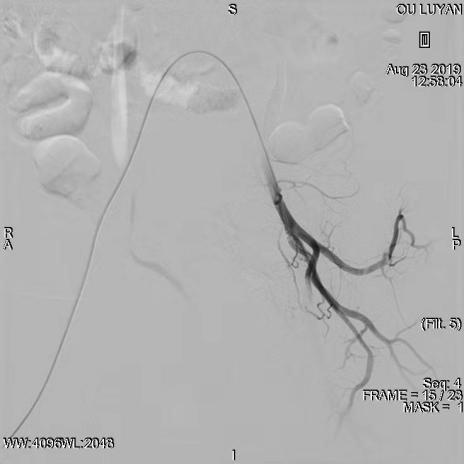

综合评估后考虑患者为Ⅱ型子宫切口妊娠,与患者及家属沟通后决定选择药物杀胚同时行双侧子宫动脉栓塞术。DSA显示双侧子宫动脉增粗、迂曲,均注入150-560um明胶海绵颗粒,造影显示栓塞满意。血β一HCG下降后在宫腔镜、B超引导下清除妊娠病灶,积极终妊。8月27日,手术过程进行顺利,未输血,患者于9月1日出院,后期继续加强康复治疗,预防远期并发症宫腔粘连发生。

宫腔镜下见切口孕囊

术后超声声像